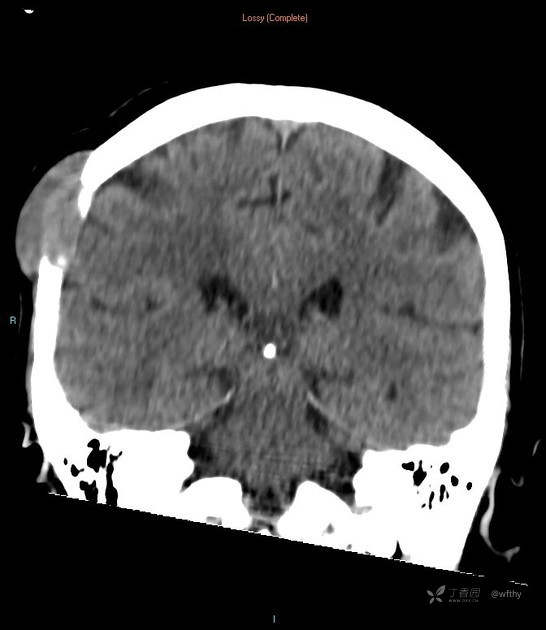

病例女65,头部肿块